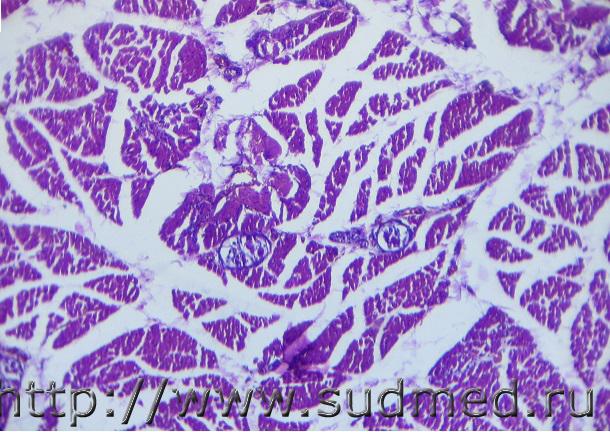

Уважаемые коллеги, помогите определиться. Взяли межрёберную мышцу и обнаружили это. Мнения разделились.

Ребёнок, 1.2 года, на протяжении последних 2-х месяцев жизни постоянно ОРВИ, осложнившиеся развитием бронхита, ДН. После последней выписки из стационара сохранялся приступообразный кашель (в диагнозе коклюш под вопросом, лабораторно не подтверждён). Умер на 4-й день после выписки во сне. Катаральный трахеобронхит, межуточная пневмония, аспирация желудочным содержимым. Фоном лимфатико-гипопластический диатез. Мышца макроскопически без изменений.

Похоже на отграниченные некрозы мышечных волокон.

Против этого : интерстициальное расположение,чёткие контуры,форма.

Вену с некротизированной стенкой напоминает или расширенный лимфатический сосуд.

Кроме того,на 2 и 6 фото ещё видны и сосуды микроциркуляторного русла с аналогичной базофильной гомогенной стенкой (некроз).

На 4 и 5 фото похоже на эндотелиальные клетки,что противоречит соединительнотканной капсуле (Вы в названии темы писали "инкапсулированное").

Первое впечатление после просмотра было о паразитарном происхождении. Второе- миозит (кроме данных образований, имеется очаговая инфильтрация в основном лимфоцитарная). Но причина? Консультировались с паразитологами и ветеринарами ... к единому мнению не пришли.